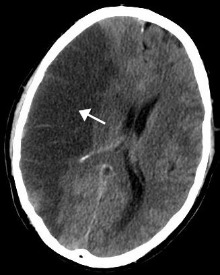

MRI demonstrating white matter changes in the brain of patients with CADASIL

CADASIL is an inherited disorder caused by mutations in the Notch 3 gene located on chromosome 19.[19] The Notch 3 gene codes for a transmembrane protein whose function is not well-known. However, the mutation causes accumulation of this protein within small to medium-sized blood vessels.[19] This disease often presents in early adulthood with migraines, stroke, mood disturbances, and cognitive deterioration. MRI shows white matter changes in the brain and also signs of repeated strokes. The diagnosis can be confirmed by gene testing.[20]